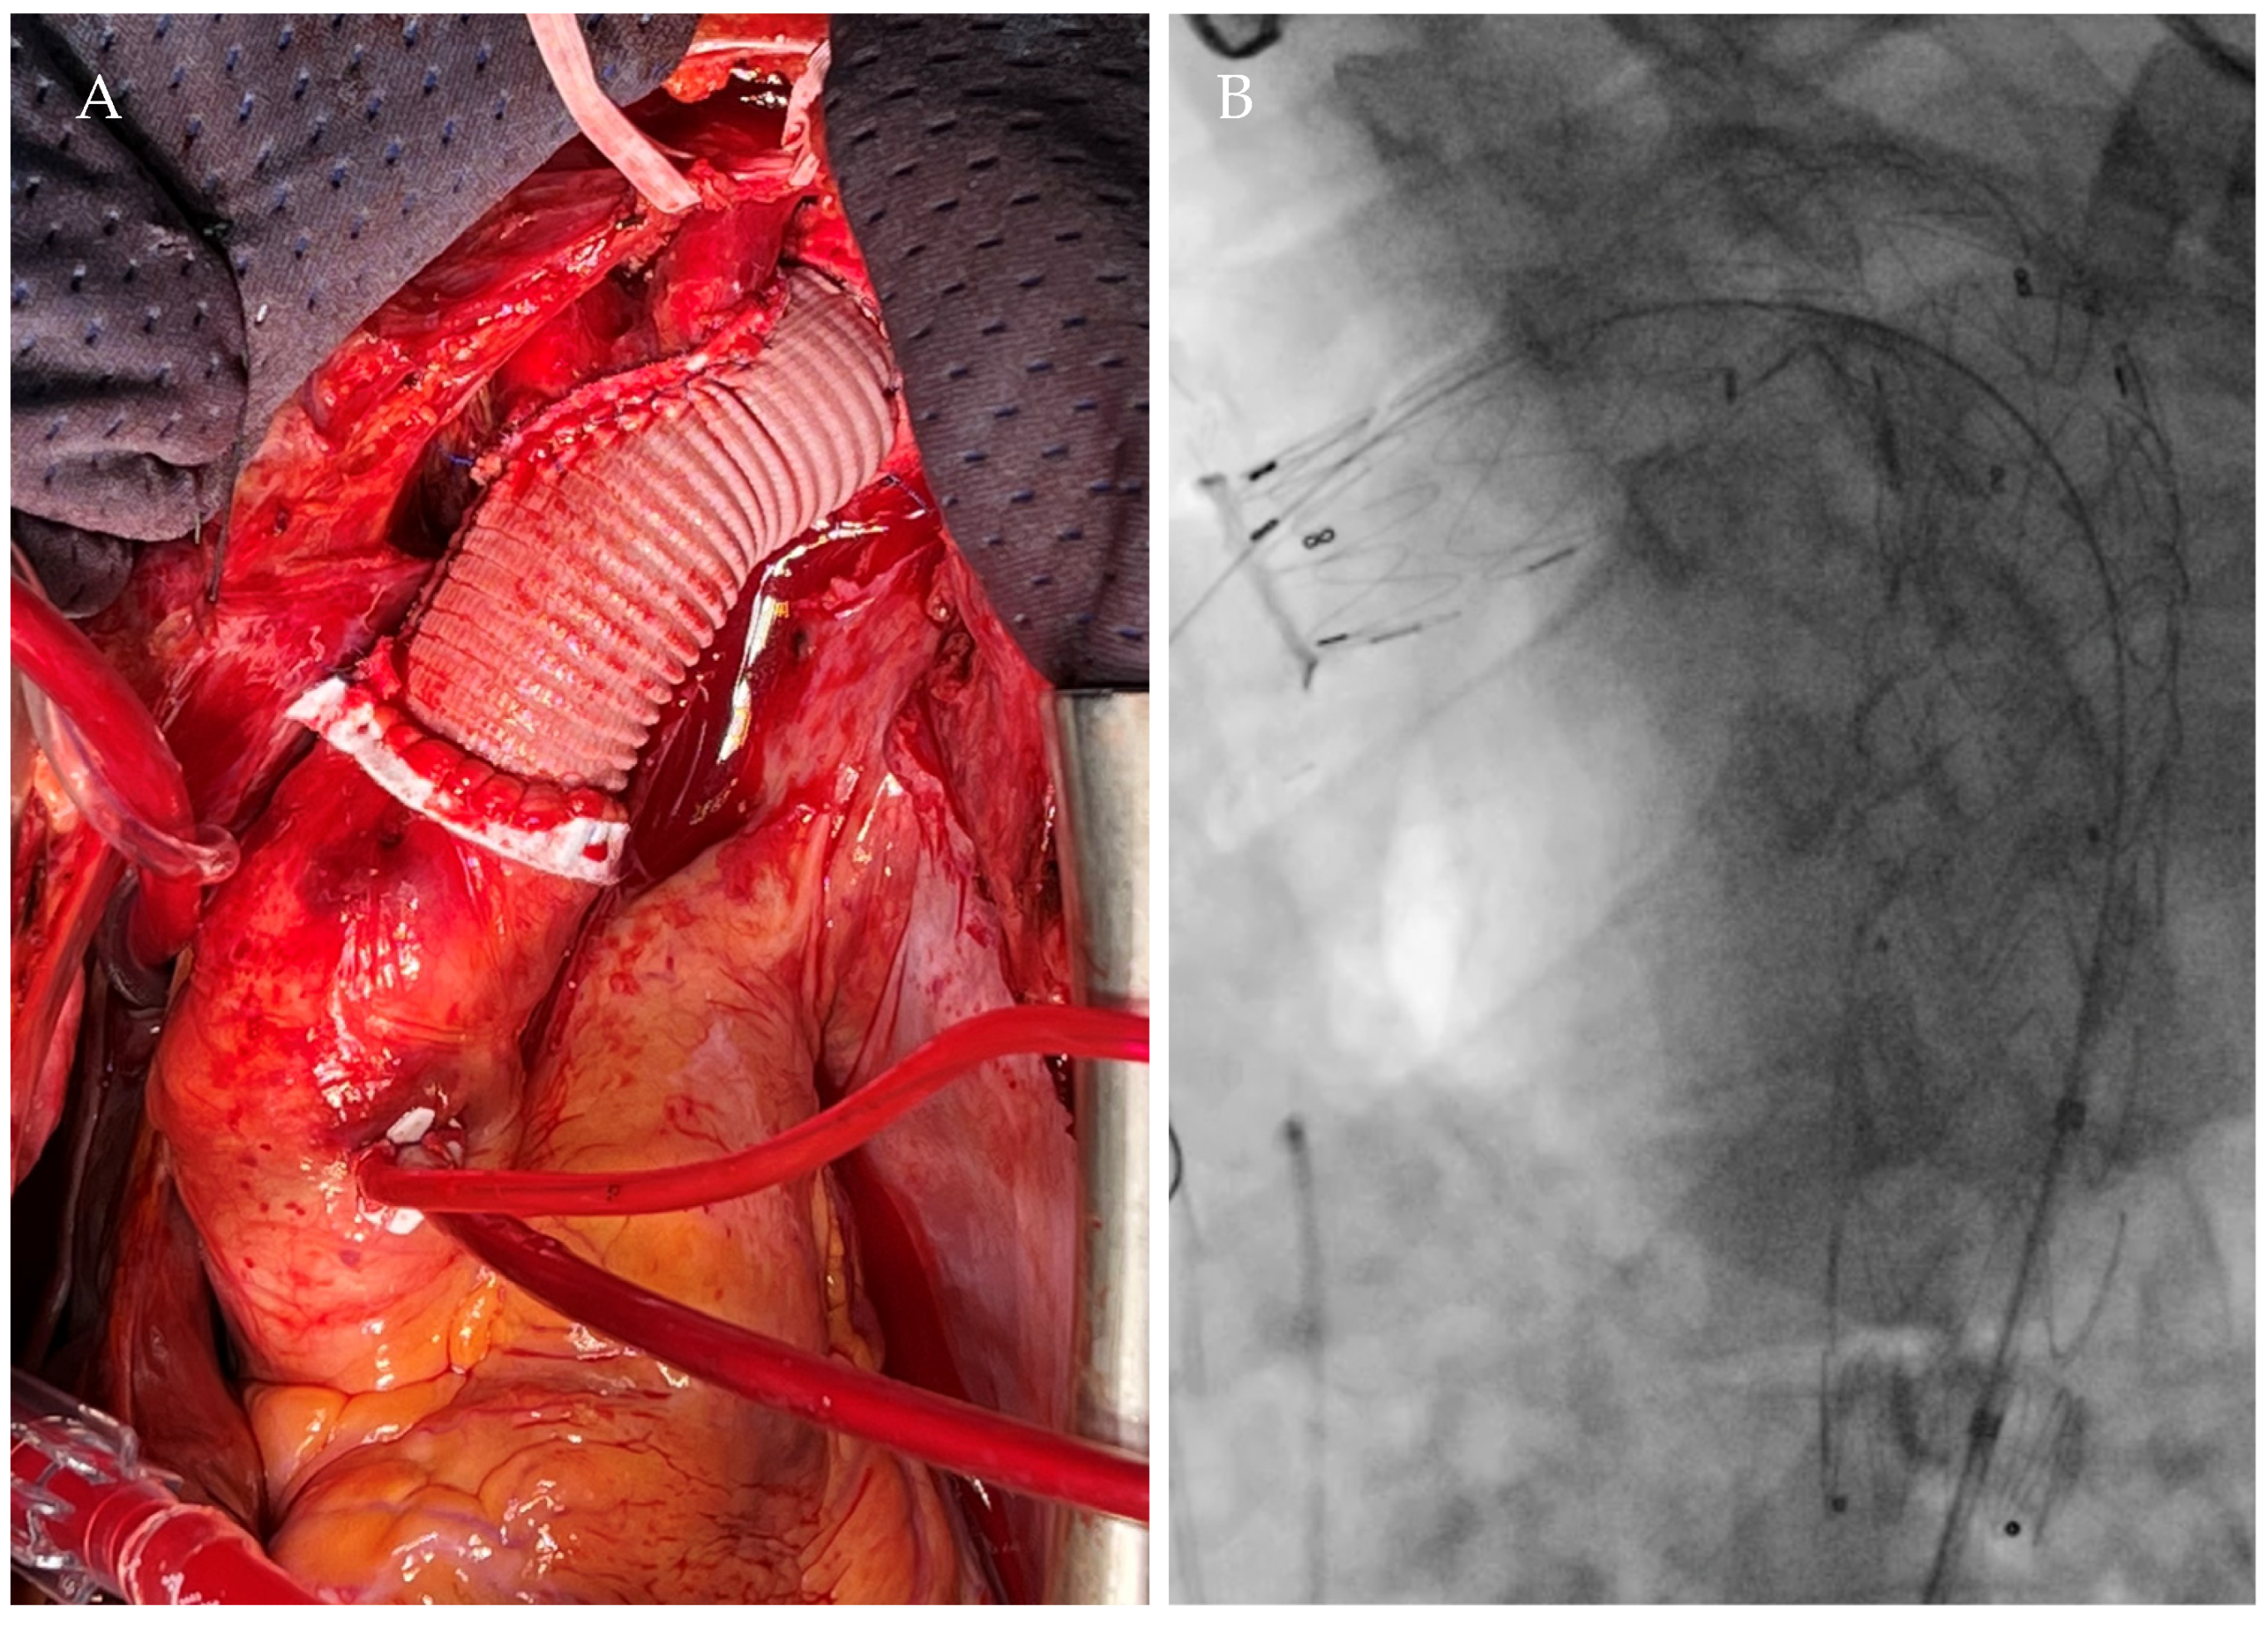

2.1. Case 1

| Current Case-1 | 48 | M | Aortic arch | Cough | 25 years | Hybrid (ET + TEVAR) |